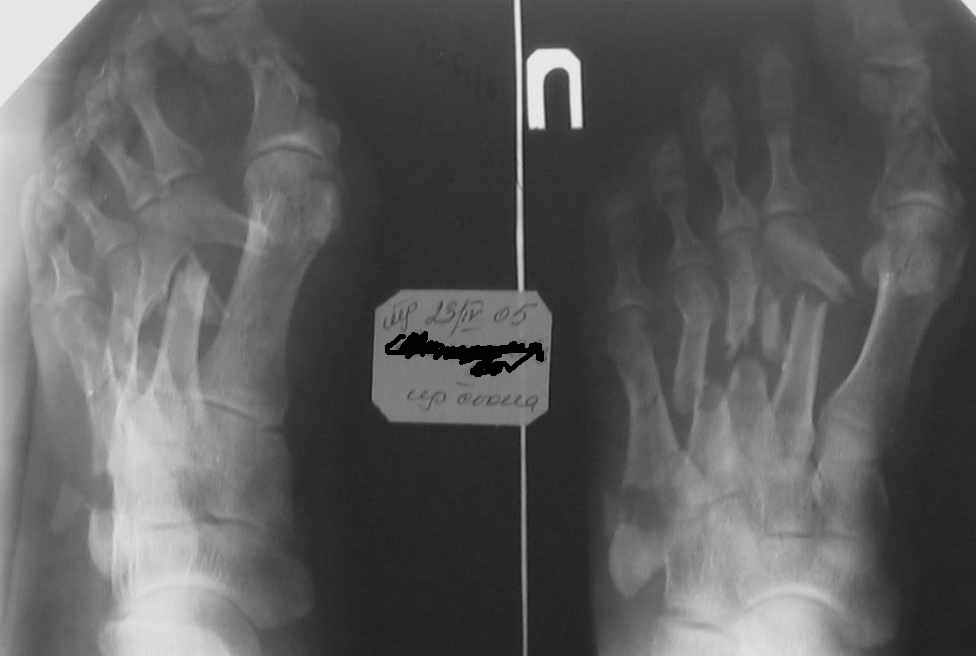

Здравствуйте, Тимур Вячеславович. Спасибо за живой интерес к проблеме: этапы к Вам понял. Насчет ампутации, я думаю, что больной еще не созрел, наоборот- полон оптимизма. Вот свежие рентгенограммы и стопа на 5 день после операции. Появились грануляции, но рана глубокая- 2-2,5 см. Хотелось бы узнать о Вашей тактике на ближайший период, если это возможно. С уважением, Алексей

Отправитель: Холиков Т. В. 09 Сентябрь 2005, 23:31

Здравствуйте, Алексей. А на самом деле все не так уж и плохо. По моему сейчас нужно купировать воспалительный процесс, добиться заживления раны а затем думать о реконструктивной операции. а пока, после появления обильных грануляций ванночки со слабым раствором марганцовки (3-4 кристаллика) до полной готовности кожных покровов (каждый день по 2-3 раза).